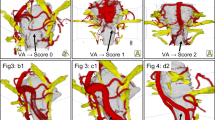

Data from eleven patients were included in this study between January and September 2020 (Supplemental table 1): six males and five females with an average age of 47 (range: 14–83). Most extraforaminal cranial nerve branches could be identified in all subjects by both observers after administration of gadolinium contrast agent, except for the lesser occipital and ophthalmic division of the trigeminal nerve where detection rates were considerably lower (Table 2). The use of gadolinium contrast significantly improved nerve detection rates on the 3D CRANI sequence when comparing combined detection rates before and after contrast administration (p < 0.001). 3D CRANI allowed us to obtain high spatial resolution (Figs. 2, 3, 4, and 5). The ophthalmic trigeminal branch and the occipital nerve branches were the most difficult to distinguish as illustrated by lower identification scores. A similar pattern was seen when nerve visualisation scores were evaluated (Fig. 6). On average, the visualisation of most cranial nerve branches was scored as good to excellent, except for the glossopharyngeal and vagus nerves and the smaller nerve branches such as the deep temporal and ophthalmic nerves which still received a fair score meaning the proximal portion of these branches could be identified. Nerve identification before contrast administration showed an overall intrarater agreement of 79.2% and interrater agreement of 82.7% (intrarater κ = .561, p < .0001; interrater κ = .642, p < .0001). After contrast administration, this improved to an overall intrarater agreement of 92.7% and interrater agreement of 93.6% (intrarater κ = .688, p < .0001; interrater κ = .727, p < .0001).

a Oblique coronal view of the 3D CRANI sequence immediately after contrast administration illustrating the lingual nerve (long arrow) and inferior alveolar nerve (short arrow) running lateral to the pterygoid muscles on an oblique coronal viewing plane. Barium filled bags were used to fixate the patient’s head and further improve the suppression quality of surrounding tissues. b Third division of the trigeminal nerve in an axial view. This illustrates the ability of the 3D CRANI sequence to visualise the buccal (arrowhead), deep temporal (small short arrow), auriculotemporal (small long arrow), and masseteric (large arrow) nerves

a Venous plexus artefacts before contrast administration limiting the visualization of the third division of the trigeminal nerve in the area of the pterygoid muscles and plexus. b Same patient as in Figs. 1, 2, 3, 4 and 5 after gadolinium contrast administration. Remarkable improvement in suppression quality and nerve visualisation. Some lymph nodes remain poorly suppressed (white arrow)